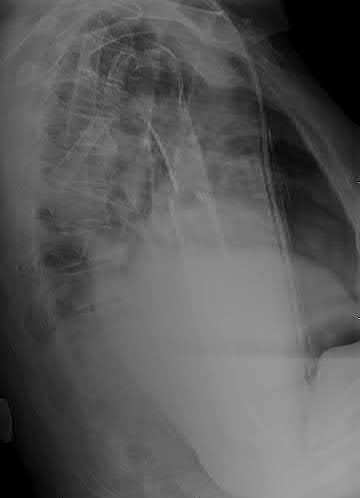

Question 11

A poly-trauma patient presents hemodynamically unstable with an anteroposterior compression (APC-III) pelvic ring injury. A circumferential pelvic binder is requested to reduce pelvic volume and control hemorrhage. To be anatomically effective, the binder must be centered precisely over which of the following landmarks?

Explanation

For optimal mechanical advantage and effective reduction of an 'open book' pelvic fracture (APC type), a pelvic binder must be applied directly over the greater trochanters of the femurs. Applying it higher, such as over the iliac crests, is a common error that fails to adequately close the pelvic ring and can paradoxically open the true pelvis.